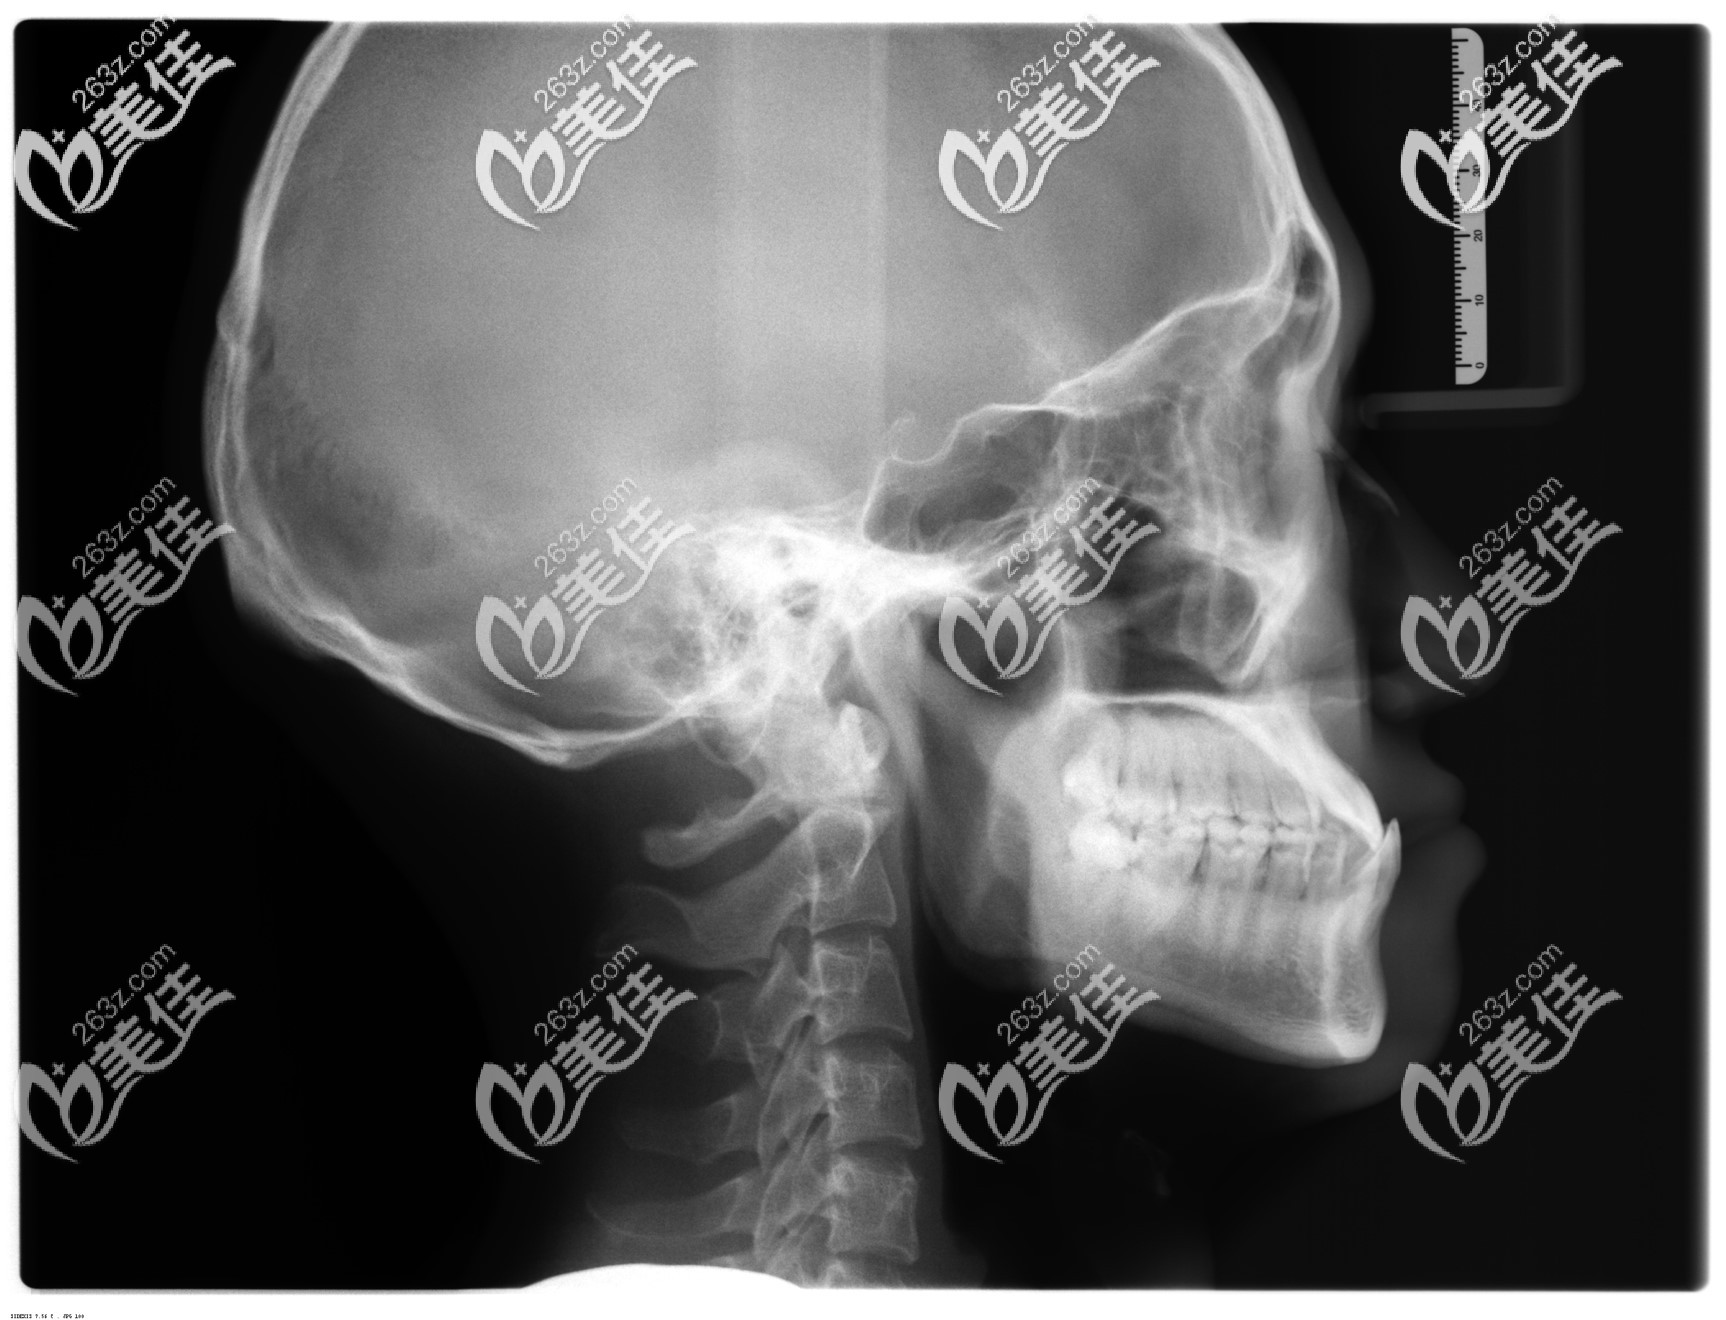

游学敏医生很专业,把我的牙齿情况分析的很到位,说我的反颌伴随着骨性成分,并不单纯是牙性的。

骨性地包天矫正前拍的口腔头颅侧位片▼

地包天骨性和牙性照片▼